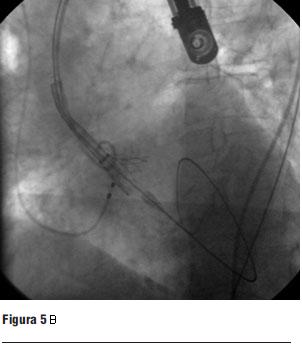

Luego de la valvuloplastia y en el menor tiempo posible se procedió al avance y posicionamiento de la válvula percutánea, con posterior liberación de la misma (figura 5 a, b, c y d).

Figura 5. Prótesis CoreValve expandida en posición aórtica.